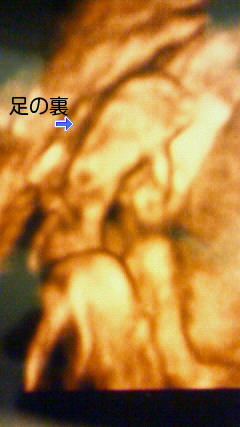

頭が写るはずの

場所に何故か

足の裏が

そうです・・・・・

逆子ちゃんです。

2週間後の検診までに元に戻ってなければ

帝王切開になるかもしれないと

医者に告げられてしまった。

何てこったい・・・・。

俺のマッサージで何とかしてやりたいが

無理っぽい・・・・・・。

そこで、院長に相談してみたところ

逆子にはお灸が効くと言う情報を入手!!

早速、俺の知ってるなかで最高の東洋マジシャン

山本先生に相談しました。

すると山本先生は力強く一言

『 息子さんは、危険な状態ですが、

僕が必ず助け出します!!

お父さん、ご安心下さい!! 』

何て頼もしいお方だ

まーそんな感じで、嫁さんは山田院長と山本先生に

2週間後の検診までお灸を据えられることになりました。

そして!!!!!

検診の結果は!?

正常に戻ってました!!

恐るべし東洋マジック!!!!!!!!!!

期待してなくてごめんなさいm(_ _)m

3000年の歴史の重みを知りました。

皆さんも東洋マジック1度ご賞味あれ!!!

人生が変るかもしれませんよ☆

そして我が子は、こんな感じになっちゃいました!!!!